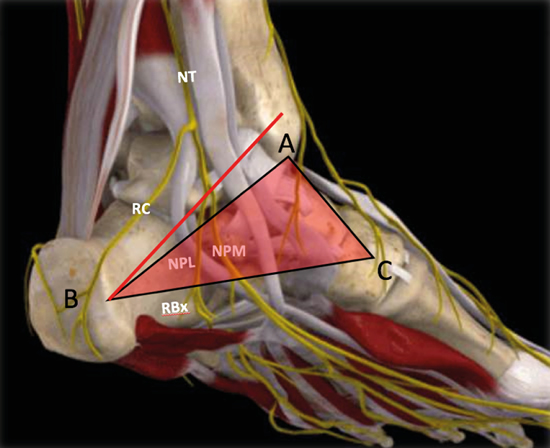

Figura 3. Túnel tibiotalocalcáneo. El nervio tibial (NT) se divide en la rama calcánea (RC), el nervio plantar medial (NPM) y el nervio plantar lateral (NPL) del que se escinde la rama de Baxter (RBx). Las estructuras musculotendinosas tibial posterior (TP), flexor largo del primer dedo (FLD) y flexor largo de los dedos (FCD) acompañan al nervio tibial en su recorrido por la cara medial del tobillo y el pie. Imagen modificada de la App Ankle & Foot Pro III.

No obstante, la visualización de los nervios plantar medial y plantar lateral es más evidente cuando se avanza hacia distal. Para ello se mantiene la sonda en eje corto (Figura 13) tomando como referencia la tuberosidad posterior del calcáneo, de donde parten el eje de Dellon-Mackinnon4 y el triángulo de Heimkes (área entre tuberosidad del calcáneo, el vértice del maléolo medial y el navicular)8 (Figura 12).

Figura 13. Línea de Dellon-Mackinnon (A-B) y triángulo de Heimkes (A-B-C). Se observan el nervio tibial (NT) y las ramas calcánea (RC), el nervio plantar lateral (NPL), el nervio plantar medial (NPM) y la rama de Baxter (RBx). Imagen modificada de la App Ankle & Foot Pro III.